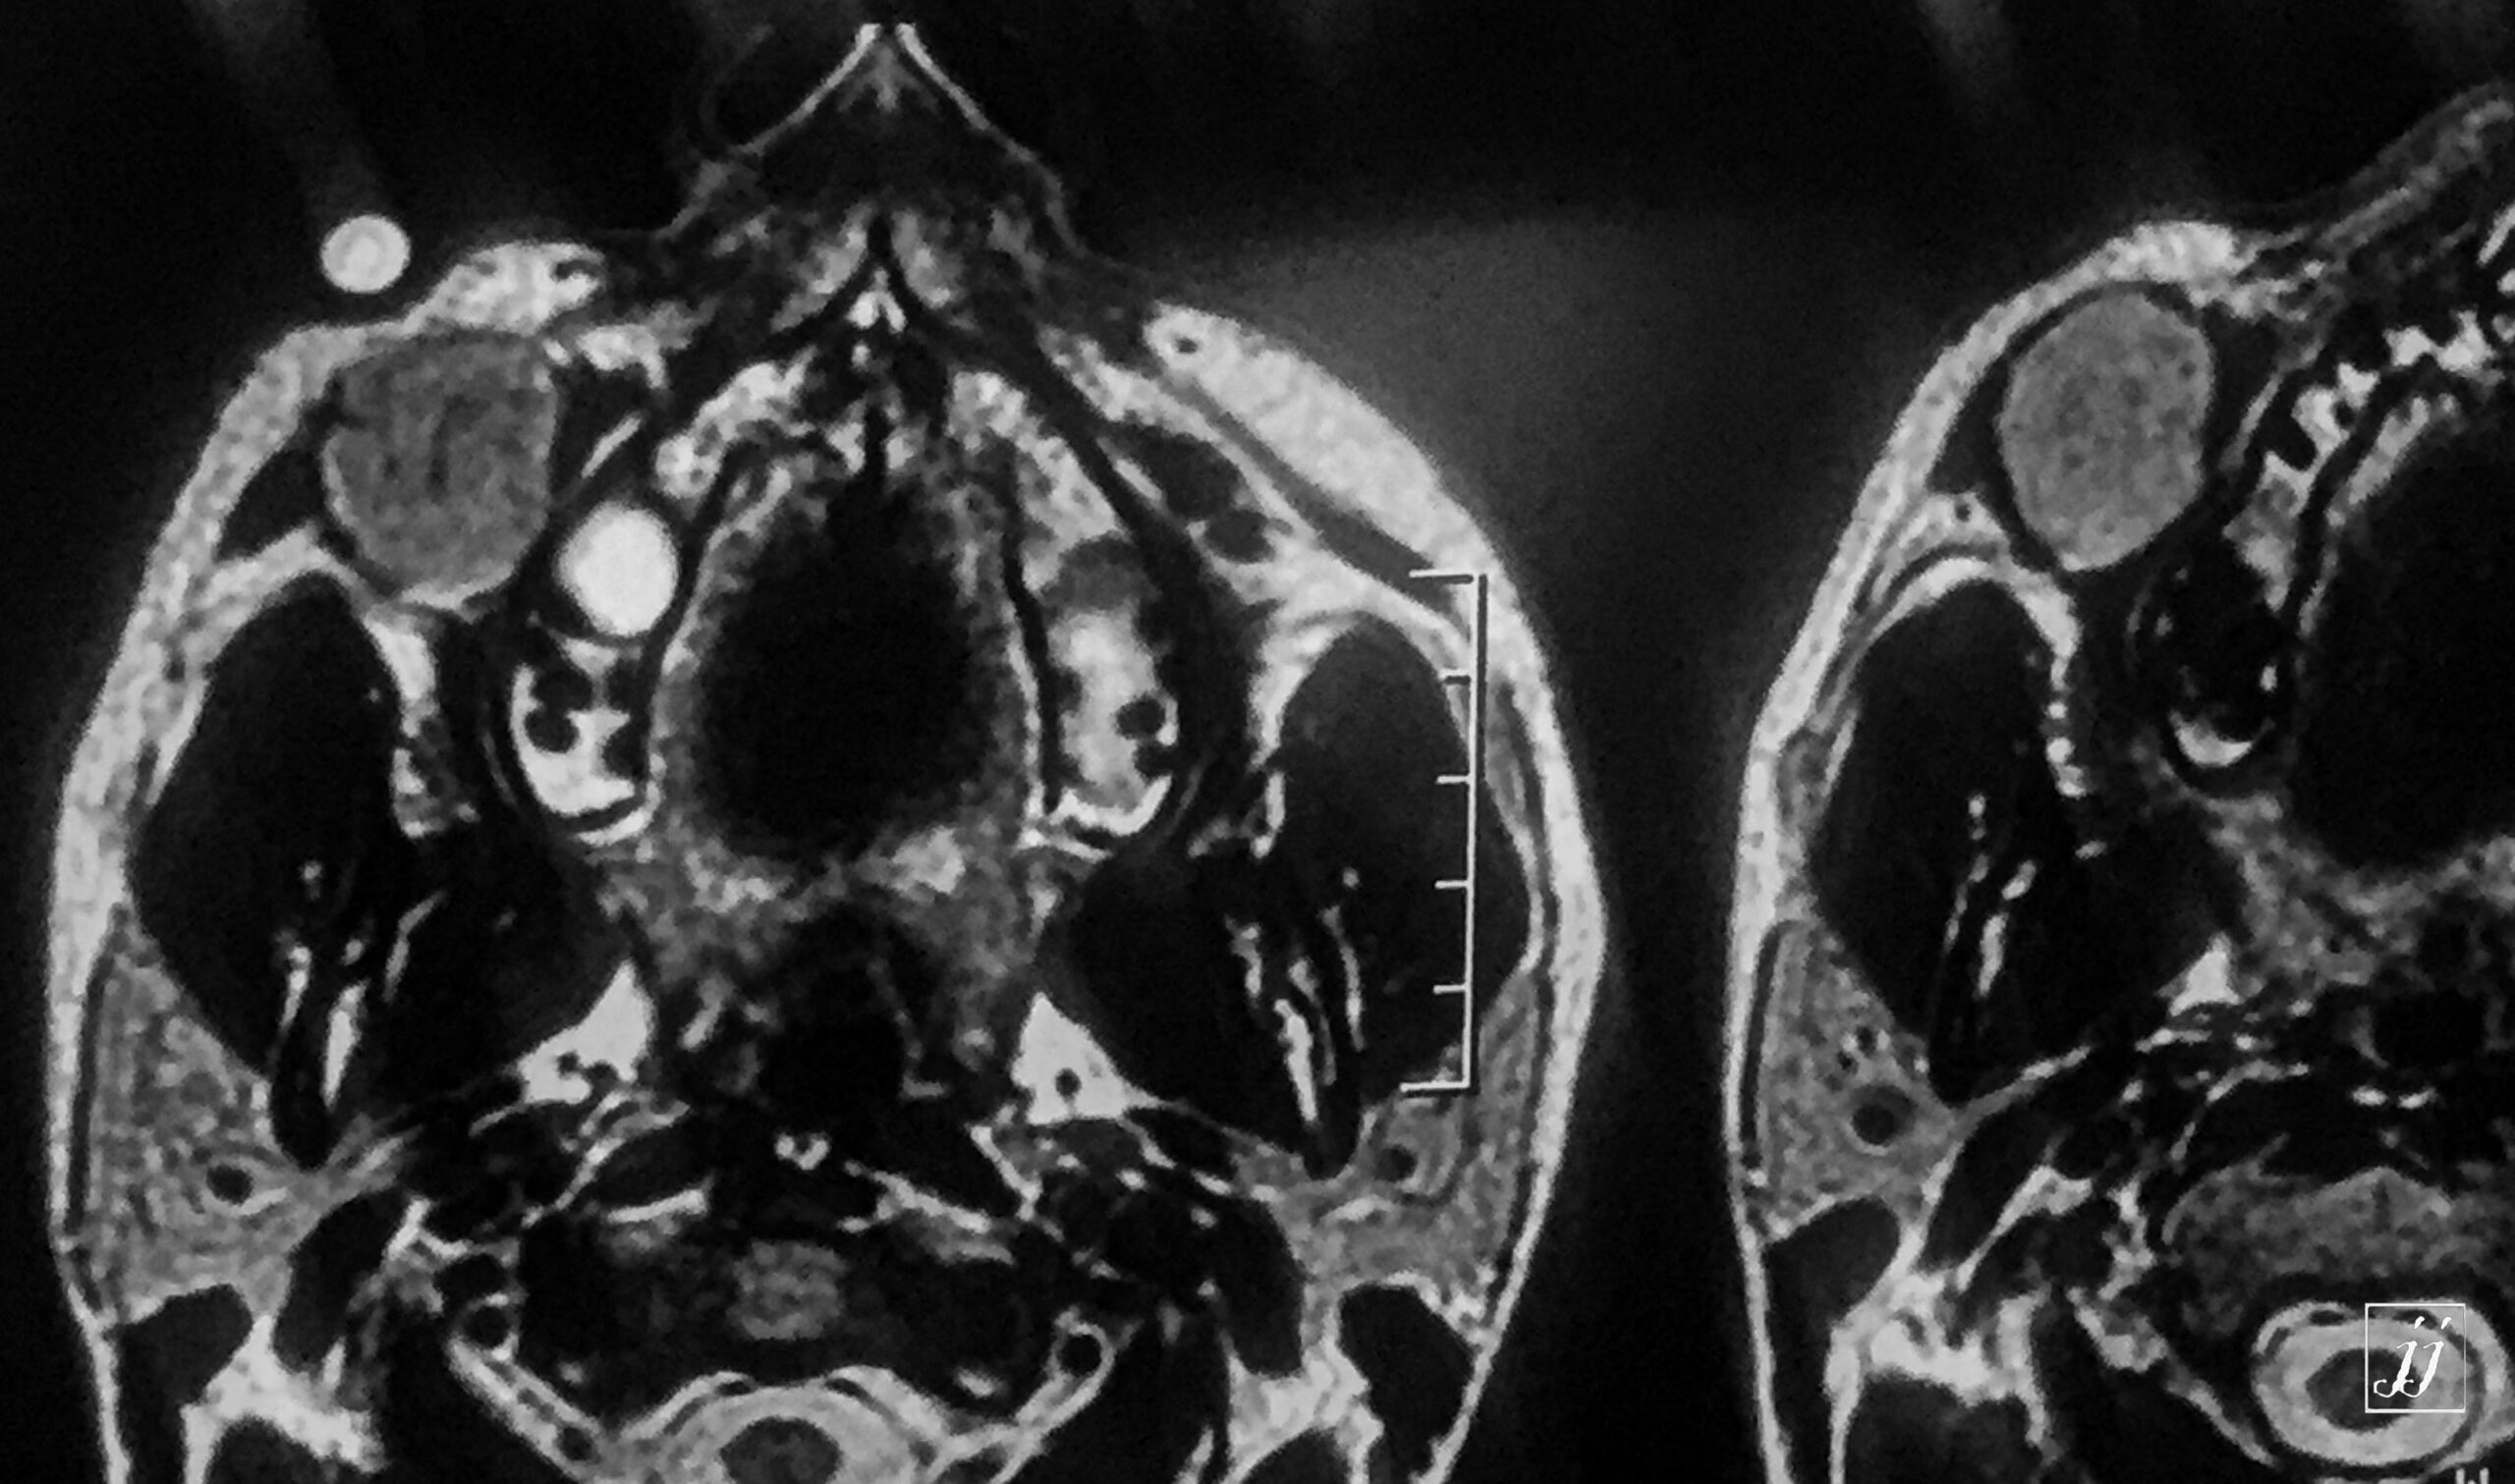

Orbit- right maxillary sinus retention cyst (6)